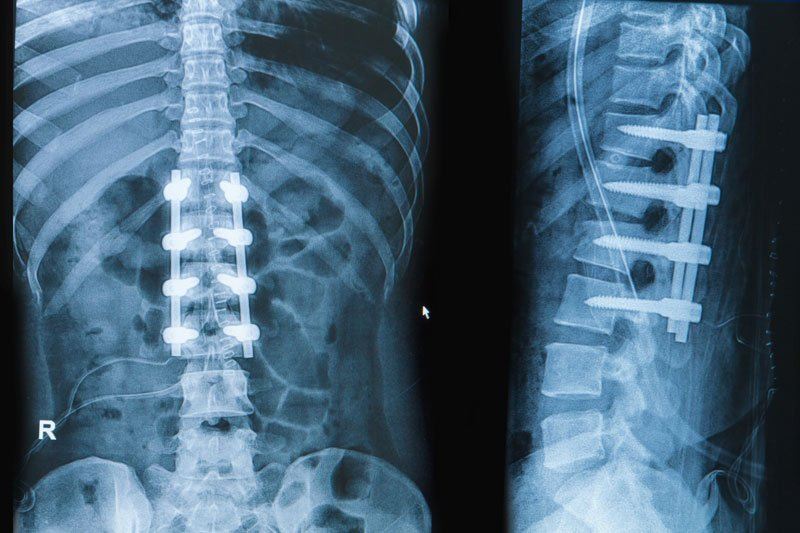

• Spinal Fusion: A surgical procedure that fuses two or more vertebrae to provide stability and reduce motion at the affected segment of the spine.

• Artificial Disc Replacement: In some cases, a damaged disc may be replaced with an artificial one to maintain spinal mobility.